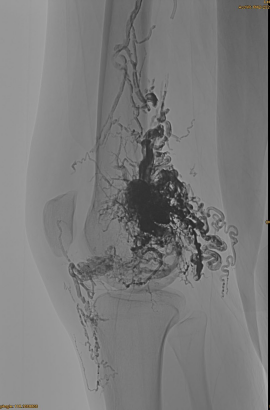

DSA ראשוני:

תוצאה סופית:

בקושי שום יצוא ורידי:

שלב מאוחר, EMBO נוסף הכרחי, אך הרבה יותר טוב: